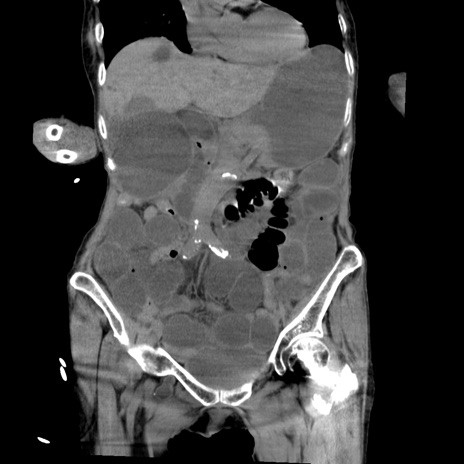

横断像

【症例】80歳代女性

【主訴】嘔吐、腹痛

【現病歴】数時間前より嘔吐あり。心窩部痛出現し、徐々に右下腹痛あり。その後も数回嘔吐あり救急搬送となる。

【既往歴】左大腿骨頚部骨折手術

【身体所見】腹部は膨隆しているが軟らかく圧痛なし。腸雑音はやや亢進。

【データ】WBC 12000、CRP 19.05